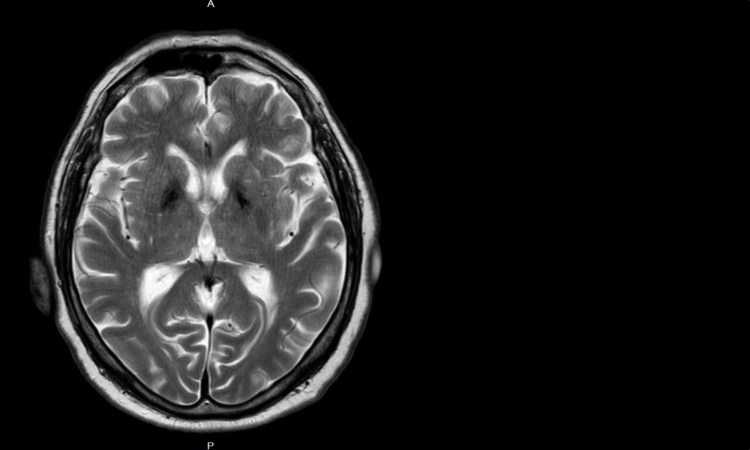

Parkinson für Dummies 03: Braak & Co. Wie geht eigentlich Parkinson?

Neurodegenerative Krankheiten: WYSIWYG oder nicht? Die Sache mit den Tauopathien und den Synukleinopathien.

Windows 95 und neurodegenerative Erkrankungen Den WYSIWYG-Vergleich wollte ich schon ganz lange machen. Heute soll es um neurodegenerative Erkrankungen gehen und um die Frage, ob es auch wirklich Parkinson ist, wenn es wie Parkinson ausschaut. WYSIWYG ist ja so ein Begriff der ungefähr aus der Ära von Karl Klammer und Windows 95 kommt. Ganz kurz…